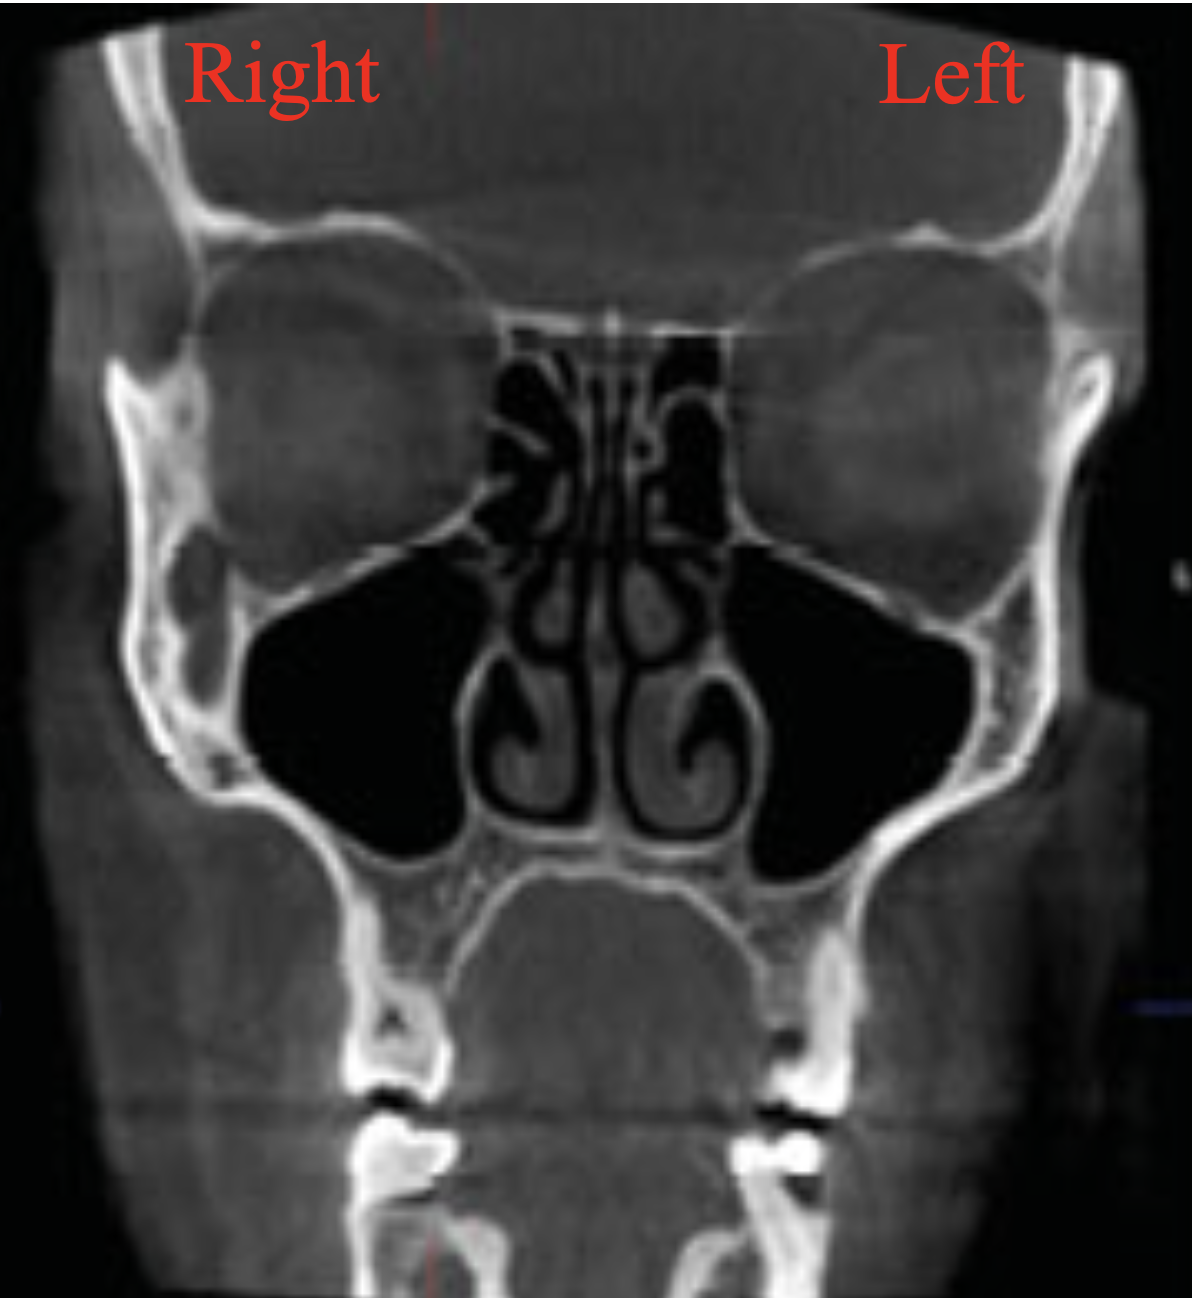

5

Q

What view?

A

Coronal